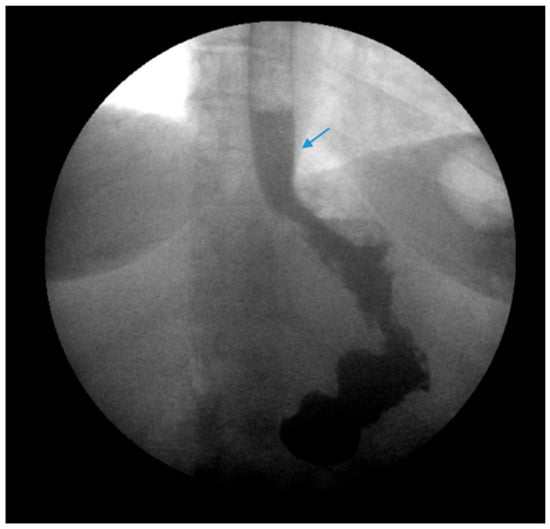

Figure 9.

Laparoscopic image reveals a patient post-sleeve gastrectomy with a defect in the diaphragmatic hiatus (arrow) and subsequent gastroesophageal reflux disease. Image courtesy of Dr. Brian Louie, Chief of Thoracic Surgery at Swedish Medical Center in Seattle, Washington, USA.

Figure 10.

Laparoscopic image demonstrates hiatal hernia repair and successful placement of a magnetic sphincter augmentation device (arrow) around the esophagus in a patient post-sleeve gastrectomy with gastroesophageal reflux disease. Image courtesy of Dr. Brian Louie, Chief of Thoracic Surgery at Swedish Medical Center in Seattle, Washington, USA.

Magnetic sphincter augmentation (MSA) devices, such as the LINX© system, have also been used as an experimental approach to mitigate post-SG GERD. MSA devices utilize titanium beads with a magnetic core connected with titanium wires to form a ring shape, which is laparoscopically placed around the lower esophageal sphincter as a reinforcement (Figure 9 and Figure 10). Some studies have revealed favorable results [96,97,98,99,100]. A meta-analysis of three studies with a total of 33 patients revealed a pooled mean difference between preoperative and postoperative GERD-Heath-Related Quality of Life Questionnaire (GERD-HRQL) scores to be 17.5 following MSA [101]. However, data are limited. Further studies are warranted to establish the safety and efficacy of MSA devices following SG.